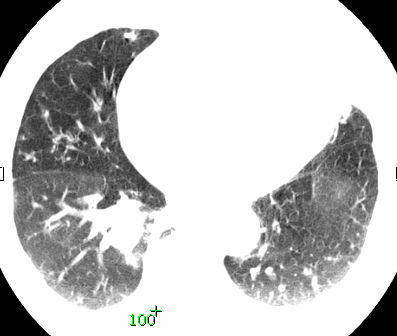

标题: CT26680:肺部右下肺静脉干结节的界定 [打印本页]

标题: CT26680:肺部右下肺静脉干结节的界定

经追查说有支扩咯血病史,但不确定